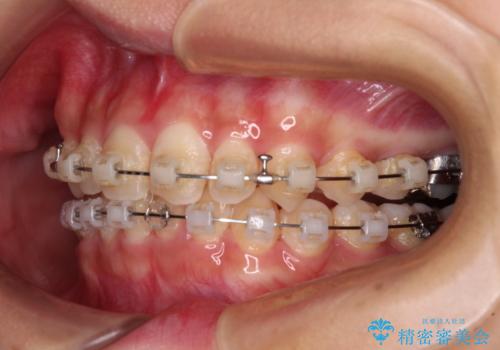

- 矯正装置

- クリアブラケット

- 治療期間

- 2年1ヶ月

- 前歯のデコボコと深い咬み合わせを改善したいとのことで来院された患者様です。

奥歯の咬み合わせは上顎に対して下顎が後方位にあり、上顎前歯で下顎前歯が隠れるような典型的な過蓋咬合です。

補助装置を用いて上顎大臼歯を後方に移動させながら、ワイヤー装置で歯列を整えて深い咬み合わせを挙上することとしました。

下顎の装置が頻繁に脱落し、治療は難航しましたが、当初予定の2年間で無事に治療を終えることができました。